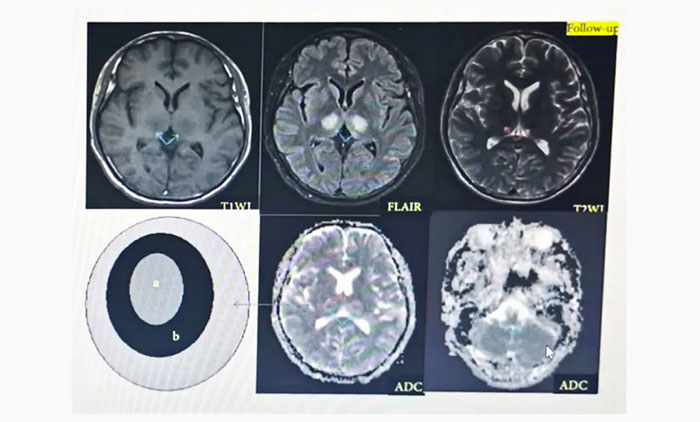

女子反应迟钝,如电脑“宕机”,原来是患罕见性脑病,张静波团队联手诊治带来希望

神经内科7A病区张静波主任介绍,ANE发病机制并不十分清楚,国际上比较公认的是细胞因子增高导致大脑继发性损害,若能积极控制细胞因子水平,将有望改善预后,关键在于在神经系统损坏不可逆之前,及时发现...【详细】